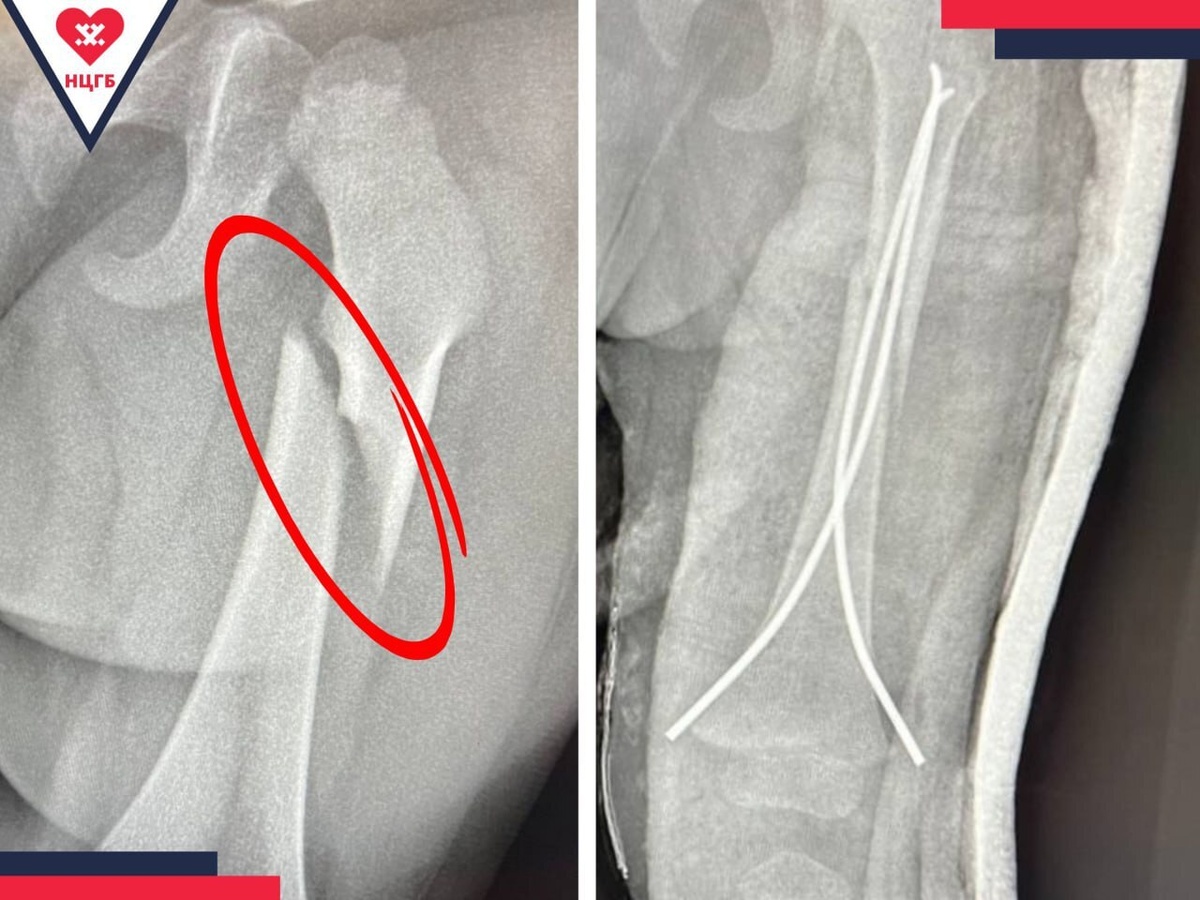

Новоуренгойские травматологи провели сложную операцию годовалому пациенту

Мальчик Амир (1 год 8 месяцев) поступил в больницу с переломом бедра. Врачи-травматологи Сергей Лазарев и Азер Самедли успешно выполнили закрытый остеосинтез — операцию через 5-миллиметровый разрез в нижней части бедра.

С помощью специальных инструментов кость была зафиксирована титановым гибким стержнем.

Метод считается «золотым стандартом» лечения переломов бедра у детей. Реабилитация займёт около месяца в гипсе, после чего стержень будет удалён. Благодаря грамотно проведённой операции травма не повлияет на дальнейший рост и качество жизни ребёнка.